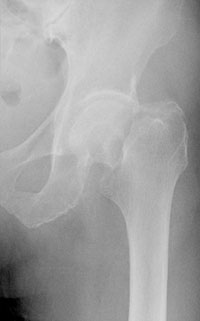

大腿骨転子部骨折に対しては髄内釘による骨接合術を施行(図1-1)、ずれの大きい大腿骨頚部骨折に対しては人工骨頭挿入術を施行(図1-2)し、なるべく早く手術をすることで患者さんの負担を軽減し、また術後の離床を促すことで合併症の予防にも繋がります。

(図1-1)大腿骨転子部骨折に対する骨接合術